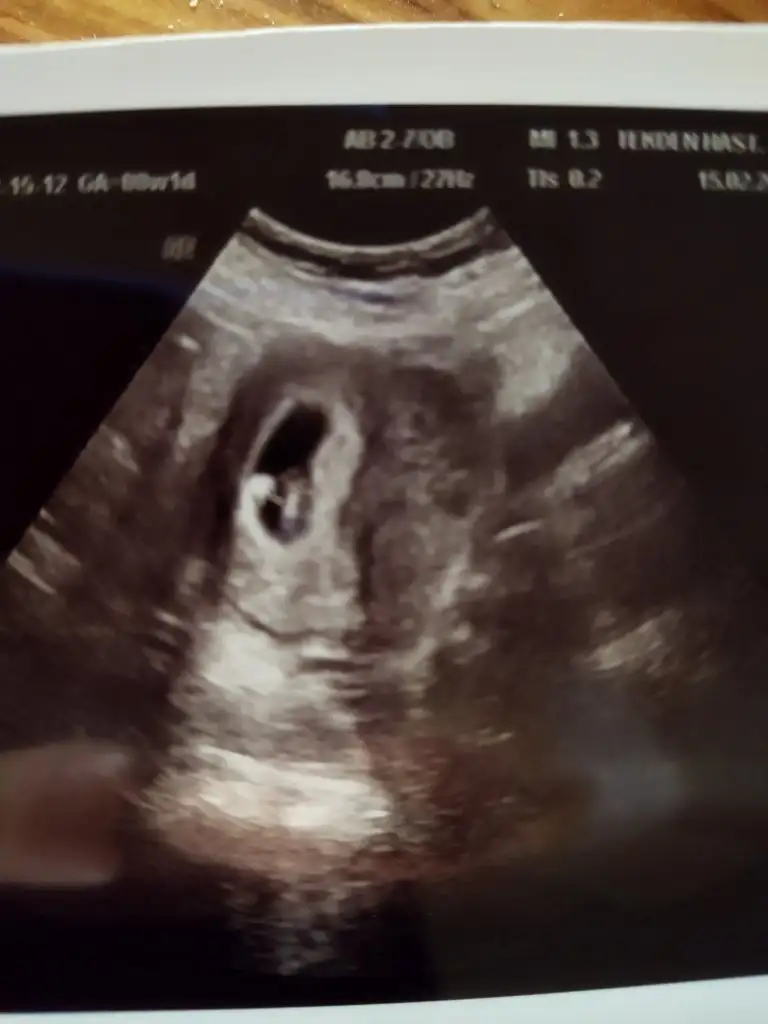

Merhaba millet

Ramzi teorisine göre cinsiyet tahmini yapacagim ilk ultrasyon resminizi atin bakiyim. Eger cinsiyetiniz belliyse hic söylemeeyin bakalm dogru tahmin edebilecekmiyim daha dogrusu ramzi teorisi hakli cikacak mi?

• IMG_20220306_141206.webp

IMG_20220306_141206.webp

20,1 KB · Görüntüleme: 77

• IMG_20220215_154452.webp

IMG_20220215_154452.webp

29,4 KB · Görüntüleme: 68